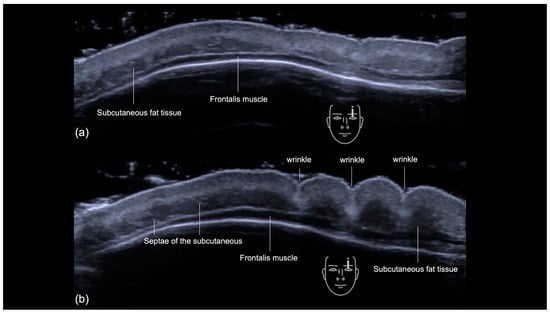

3.2.1. Sonographic Anatomy

- Epidermis: a hyperechoic line.

- Upper dermis: a hypoechoic homogeneous layer.

- Lower dermis: a hyperechoic layer.

- Subcutaneous fat tissue: a hypoechoic layer composed of fat lobules and hyperechoic septae.

- Frontalis muscle: a hypoechoic band-like structure.

- Periosteum and subfrontalis fascia: a hyperechoic line showing combined imaging of these structures, with acoustic shadowing below. Due to the convexity and reflective nature of the frontal bone, there is usually a mirror imaging artefact.